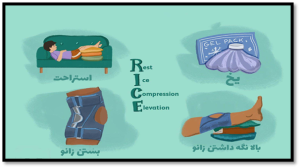

برای سرعت بخشیدن به درمان میتوانید از روش RICE استفاده کنید. روش RICE به معنای روش محافظه کارانهای است که از چهار بخش اصلی تشکیل شده است که درباره هر کدام، توضیح مختصری خواهیم داد (تصویر شماره ۸).

- استراحت یا rest: سعی کنید چند روز به زانوی خود استراحت دهید و فشاری به آن وارد نکنید.

- یخ یا ice : یخ می تواند درد و تورم زانو را کاهش دهد. از یک بسته سرد، یا یک حوله پر از تکه های یخ برای حدود ۱۵ دقیقه هر بار استفاده کنید.این کار را هر ۴ تا ۶ ساعت یک یا دو روز اول و سپس هر چند وقت یکبار انجام دهید.

- Compress یا بستن : زانوی خود را ببندید؛ برای کنترل تورم از یک بانداژ الاستیک یا یک پارچه تمیز دیگر روی زانوی خود استفاده کنید؛

- Elevate یا بالا قرار دادن :زمانی که نشستهاید یا دراز کشیدهاید، یک بالش زیر پایتان بگذارید و زانوی خود را بالاتر سطح بدن قرار دهید.

(تصویر شماره ۸) : تکنیک RICE